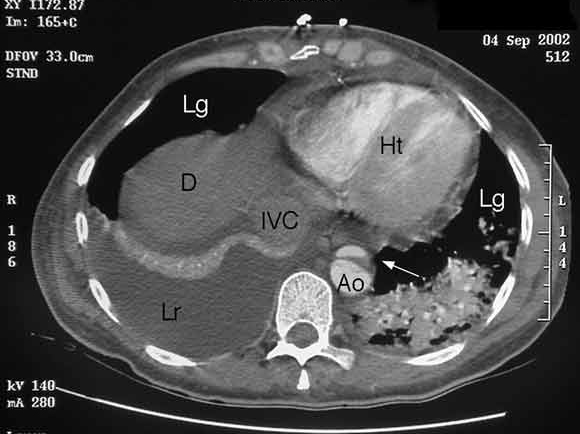

Aortic dissection in Turner syndrome

Colin I Clement, John Brereton and Phillip Clifton-Bligh

Med J Aust 2004; 180 (11): 584. || doi: 10.5694/j.1326-5377.2004.tb06097.x